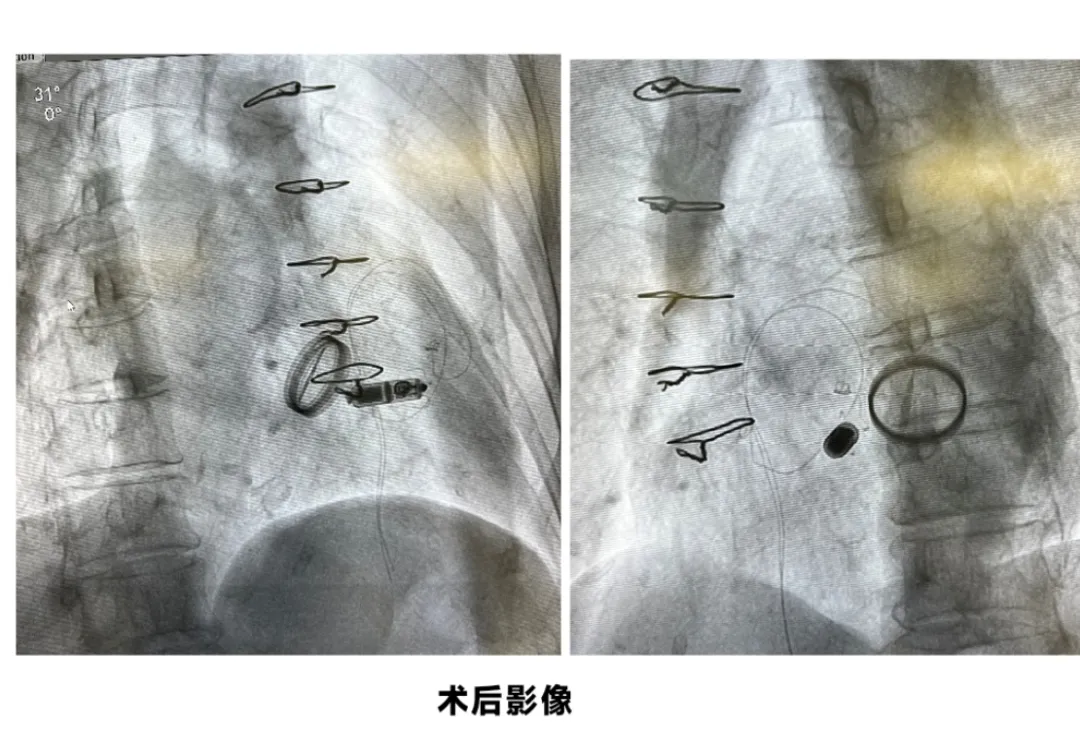

在充分评估患者病情并与其家属沟通后,心血管内科团队决定采用无导线起搏器进行植入。手术过程耗时约30分钟。术中通过股静脉穿刺建立通道,将起搏器通过导管精准植入到心腔内部。手术全程无切口、无导线、无需制作皮下囊袋,有效规避出血及感染风险。患者术后12小时即下床活动,目前已康复出院。